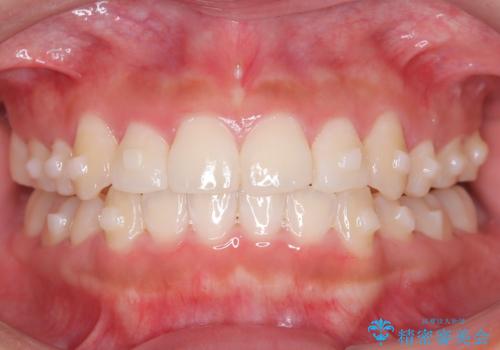

- 1年1ヶ月

マウスピース矯正治療を選択しました。

奥歯の噛み合わせは綺麗に噛んでいたため、前歯の叢生(でこぼこ)を、短期間で治療完了するように計画しました。